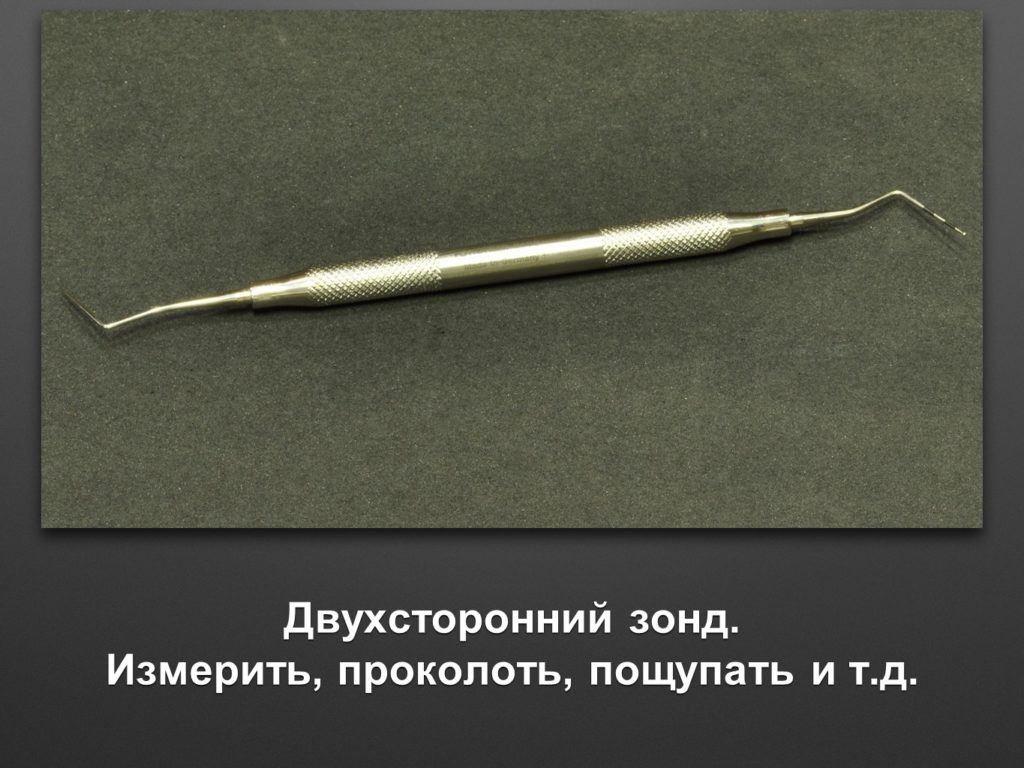

"Выстраданные" наборы инструментов

Все ниже перечисленные инструменты можно приобрести на сайте kohlermed.ru или связаться с нашим менеджером по тел 499-5179401

Все ниже перечисленные инструменты можно приобрести на сайте kohlermed.ru или связаться с нашим менеджером по тел 499-5179401